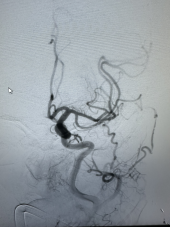

近日,广元市第一人民医院神经内科介入团队成功为91岁高龄患者实施急诊脑血管造影+机械取栓术,及时开通血管,改善了患者的症状。这是医院首次完成91岁超高龄老人急性脑缺血性卒中机械取栓术,老人术后恢复超预期,创造生命奇迹的同时,也再次彰显了医院卒中团队过硬的综合实力。

随即,卒中介入团队快速启动急诊手术流程。11:42,经介入治疗后,梁大爷闭塞血管顺利开通。再次造影显示,患者左侧大脑半球血流恢复。大脑在重新得到新鲜血液灌溉后,因缺血而不完全坏死的脑细胞逐渐恢复生机。